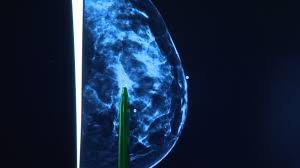

How To Know If You Have Breast Cancer Quiz : Test Your Knowledge Of The Latest Advances In Breast Cancer Research : Published on:17 october 2020, 17:19pm ist.. Our online breast cancer trivia quizzes can be adapted to suit your requirements for taking some of the top breast cancer quizzes. Gently feel your breast with your fingertips. Women with a strong family history of breast cancer have a higher risk of developing the disease. No, i have never tried it before. Published on:17 october 2020, 17:19pm ist.

This Blood Test Can Detect Breast Cancer Even Before Clinical Signs Study Business Standard News from bsmedia.business-standard.com Answer these 11 questions and we'll tell you your risk of breast cancer. This gives us your risk level based on family history and other information. Once you receive the kit, you will need to take it to your healthcare provider. I was floored with the news a macmillan nurse took me into a side room gave me a leaflet said surgeon would be in touch asked if i knew my way out. Masses that are painless, irregular ; Yes, i like to have a nice glass of red wine now and then. Cancer is a serious life threatening disease. This quiz helps you decide wether to go to the doctor or just stay home.

Check Your Breasts For The Signs And Symptoms Of Breast Cancer Stapleford Community Group from staplefordcg.b-cdn.net Cancer kills thousands of people yearly and only a few live to say they beat it. In about 2 to 3 weeks, your provider will receive the results from your test, and will contact you to discuss your results and develop a plan. That's why, it's important that you keep a watch on the signs and symptoms of it. You don't have to wait until you're 40 to talk to your doctor about breast cancer, though. Nnas a nurse, you will have to know how to provide care for these patients and what nursing interventions to include in your nursing plan of care. Answers can be found below the questions. This gives us your risk level based on family history and other information. A hard lump may be a tumor.

If you have these or other risk factors, then this calculator's results will underestimate your risk. High risk refers to a woman having a 20% or greater chance of getting breast cancer in her lifetime. Our online breast cancer trivia quizzes can be adapted to suit your requirements for taking some of the top breast cancer quizzes. After discussing your hereditary cancer risk, your provider may collect a saliva sample from you. This gives us your risk level based on family history and other information. You have had a benign breast biopsy. Cancer is a serious life threatening disease. 9 you're experiencing abnormal discharge. How much do you know about breast cancer? If you feel a lump in your breast, go to the doctor immediately. Are you sick a lot? Take this brief quiz to see what myriad oncology tests may be right for you. It often feels hard, like a lemon seed, and usually immovable.